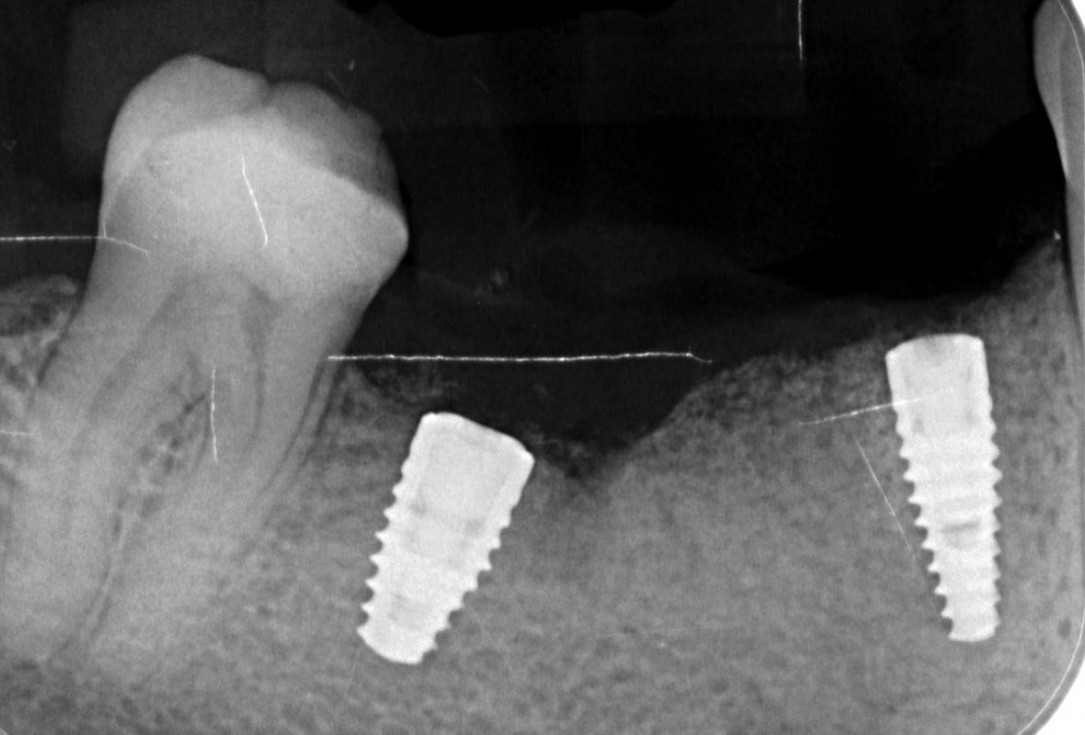

20/29 - X-ray controlVertical bone augmentation and broadening of attached gingiva using cerabone®, permamem® and mucoderm® - Dr. R. Naimoli